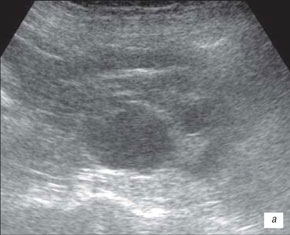

Ехограма нирки

а – запальні зміни в нирці;

б – втягнення на контурі нирки (стрілка)

На данній ехограмі ми помічаємо чіткий патологічний осередок ураження сечоводів, їх розмірів і глибину залягання.